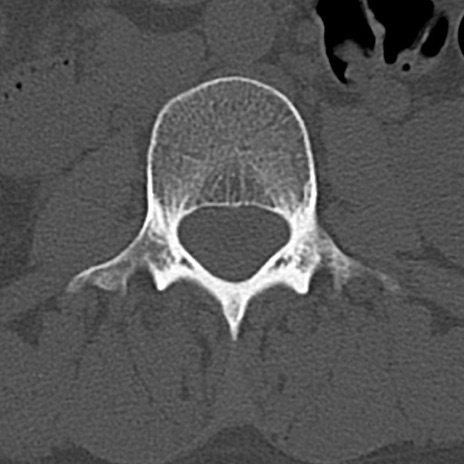

腰椎CT

横断像と矢状断像